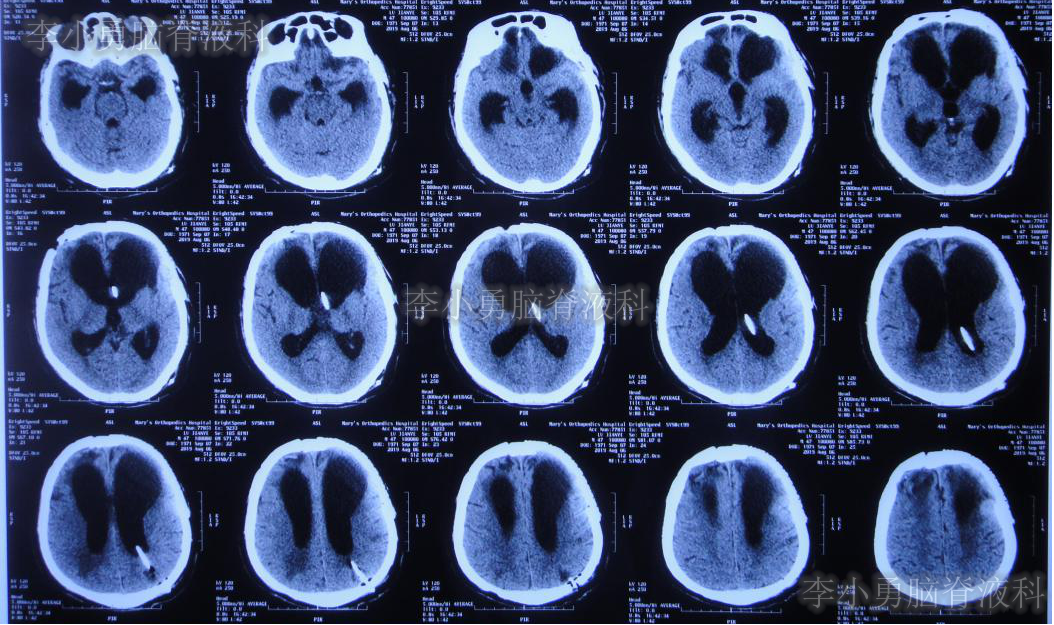

分流术后10天,即2019年10月9日,饮食变正常,神志完全清楚(图-18),常规给予复查头颅CT(图-19)示脑室进一步缩小。

图-19:2019年10月9日头颅CT脑室进一步缩小

出院后54天即2019年12月9日,复查头颅CT示脑室进一步缩小。患者智力、走路变得基本正常,但存在情感(喜怒哀乐不能表达)缺失,言语少(图-20)。

图-20:头颅CT脑室再次进一步缩小